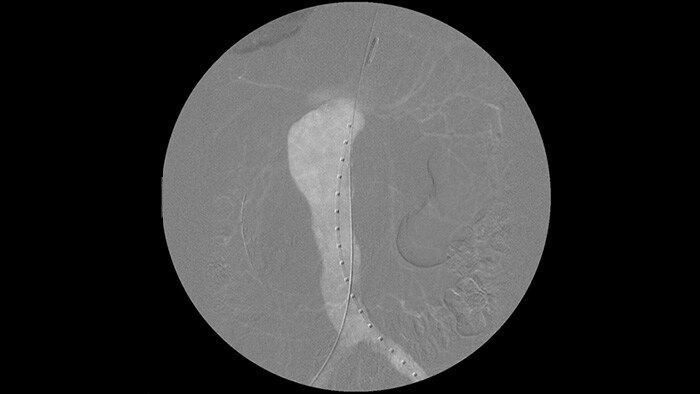

Теперь проводник увидеть легче, чем при использовании нашей старой системы. Наконечник и угол видны даже у проводников диаметром 0,014 дюйма.

Это возможно благодаря тому, что система Zenition компенсирует данные при налчии металлических объектов или движения.